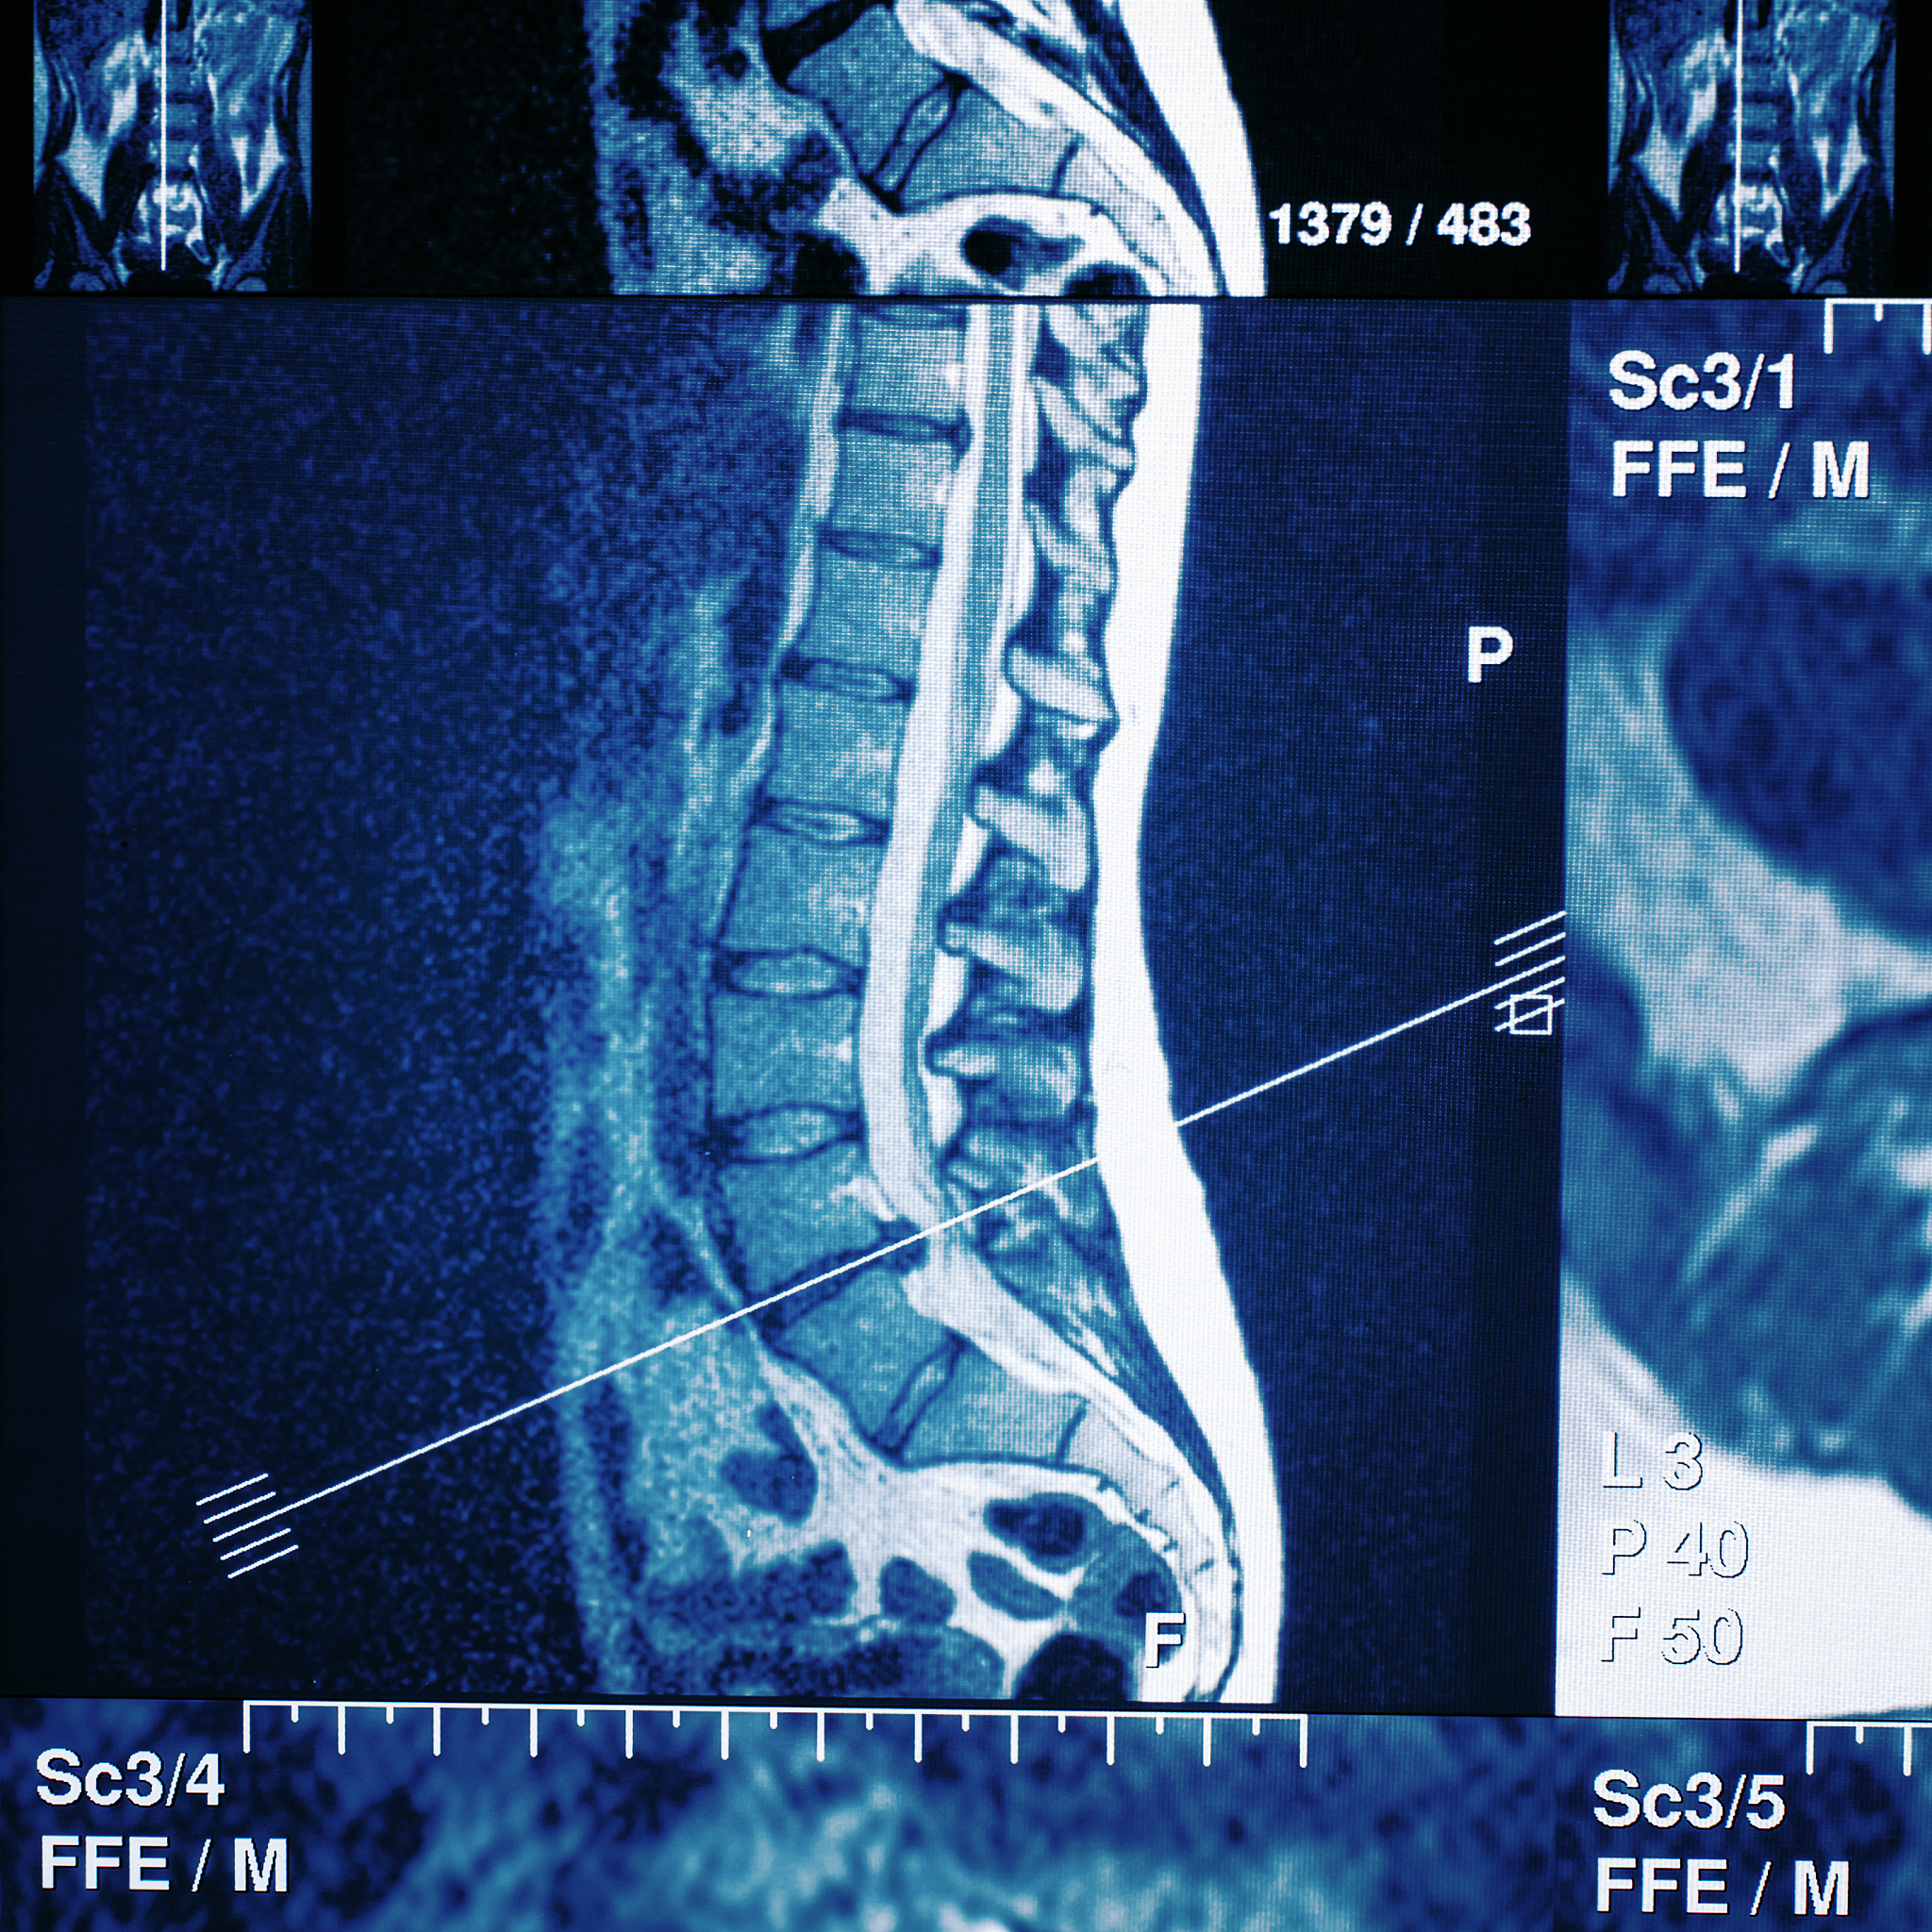

腰椎间盘突出症(Lumbar Disc Herniation)是指椎间盘的纤维环和纤维板之间的核心物质膨出或破裂,压迫或刺激周围神经根或脊髓。它是一种常见的脊椎疾病,通常会导致腰痛、坐骨神经痛等症状。